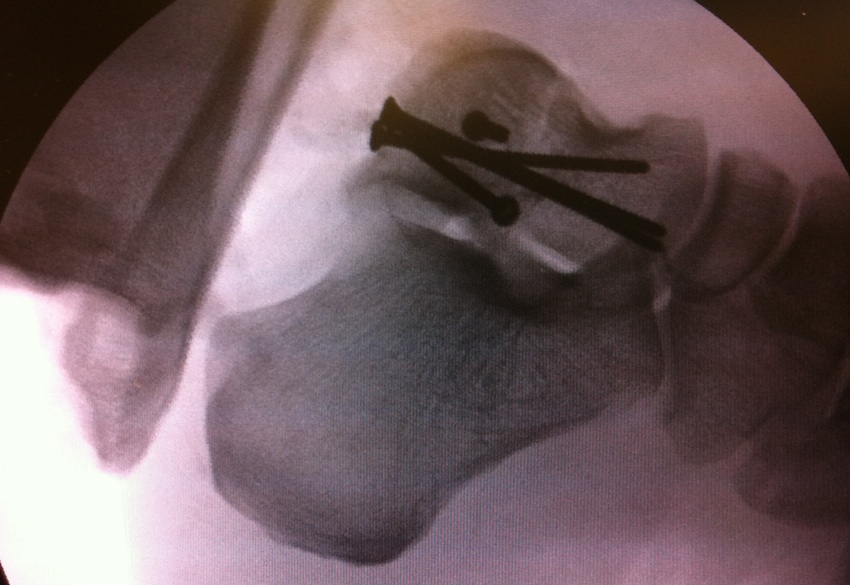

Canale view

- evaluates talar neck

- foot everted 15 deg

- look for medial shortening / varus

Cannulated screws

Xrays

| AP | Lateral | Canale View |

|---|---|---|

| Entry point of the screws |

Evaluate neck reduction

|

Evaluates the neck reduction |

Lateral off articular surface Medial through articular cartilage |

Depth of screws |

Beam angled 75o to foot Foot 15o pronated |

AP, Canale and Lateral xray